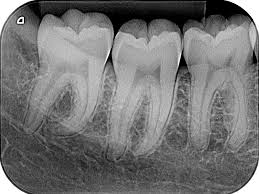

Durante el siglo XIX debido a la revolución industrial y al sin numero de avances técnicos ocurrió en la odontología una revolución que no se ha detenido hasta nuestros días .La radiología intraoral fue descubierta por Roetgen en 1895. Por ello recibió el premio Nobel de física. Otros pioneros en radiología dental fueron: Walkhof, que realizó la primera radiografía dental de la historia y Rollins, que escribió el primer texto sobre los peligros de la radiación X.

La odontología se convirtió de esta manera en una carrera muy lucrativa debido a la industria millonaria de insumos que comenzó a girar en torno a ella. En 1913 Kodak comercializó el primer paquete de película dental preenvuelta de rayos X y en 1920 se comercializaron los primeros paquetes de películas dentales hechos a máquina. Todo se volvió comercial .el equipo dental, Coolidge inventó el primer tubo de rayos catódicos en 1913. En 1923 se crea el primer aparato dental de rayos X por Victor X-Ray Corporation. Marca que aun tiene presencia en la industria de la radiología dental